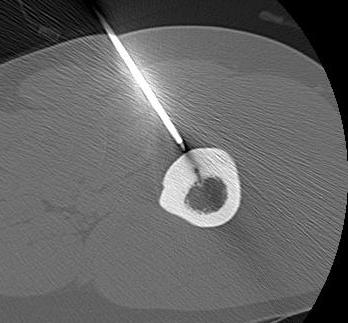

Radiofrequency Ablation

Concept

High frequency current

Thermal ablation

Technique

GA

- introduce electrode under CT

- tissue for histology

- radiofrequency

- increase temperature to 90o for 4 - 6 minutes